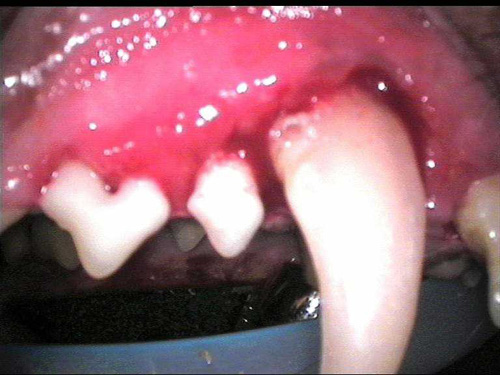

Dent tartar 1-5

destructive disorder